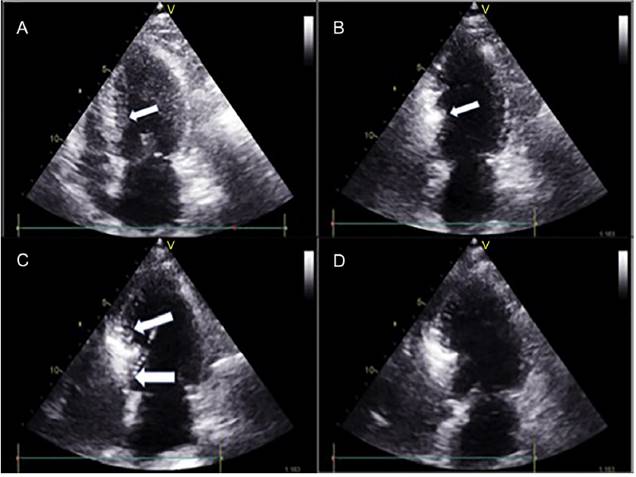

En concordancia con protocolo establecido en la institución, la paciente fue llevada a sala de hemodinámica y bajo sedación anestésica intravenosa se instaló un electrodo de marcapaso transitorio a través de punción yugular interna derecha. Se comprobó adecuada estimulación y captura y se dejó marcapaso a demanda con frecuencia de 60 lpm y salida de 6 mV. Se hizo ecocardiograma transtorácico con equipo Vivid E 9 XDclear, al igual que cateterismo izquierdo previa preparación de regiones inguinales mediante asepsia y antisepsia en forma usual. Se colocaron campos en zona de punción femoral con anestesia local con xilocaína al 2% sin epinefrina; luego de la inserción bilateral de introductores en ambas arterias femorales mediante técnica de Judkins en arteria femoral derecha e izquierda, se pasó heparina 10.000 unidades intravenosa. Por vía femoral izquierda se introdujo catéter pig-tail 6 F dejándolo en ápex del ventrículo izquierdo conectado a transductor de presiones. Por vía arterial femoral derecha se introdujo catéter guía Judkins izquierdo 6 F. Se realizó angiografía selectiva de la coronaria izquierda; se localizó la primera rama septal. Por el catéter guía, se introdujo guía metálica de 0,014 pulgadas y 300 cm de largo, posicionándola en arteria primera de la rama septal y a través de ella se pasó balón de angioplastia Apex-Push Over The Wire 1.5 mm por 8 mm, colocándose en tercio proximal de la primera septal. Se procedió a llenar balón a presión de 6 ATM dejándolo inflado a fin de ocluir la rama septal. Se retiró guía y se inyectó medio de contraste previamente hiperagitado, para realizar el contraste guiado por ecocardiograma transtorácico, delimitando la arteria septal donde se haría la ablación con alcohol (fig. 1). Con ayuda de este procedimiento se confirmó que la primera rama septal es la rama que da el flujo más significativo a la zona septal y es donde se debe hacer la ablación.

Figura 1 Ecocardiograma bidimensional que muestra la marcación del septum con medio de contraste hiperagitado. A) Imagen ecocardiográfica bidimensional que muestra el septum interventricular hipertrófico antes de pasar el medio de contraste. B) Inicio del paso del medio de contraste por la arteria primera septal comenzando a demarcar la zona septal de mayor irrigación. C) Inicio de la colocación del alcohol en la primera rama septal.